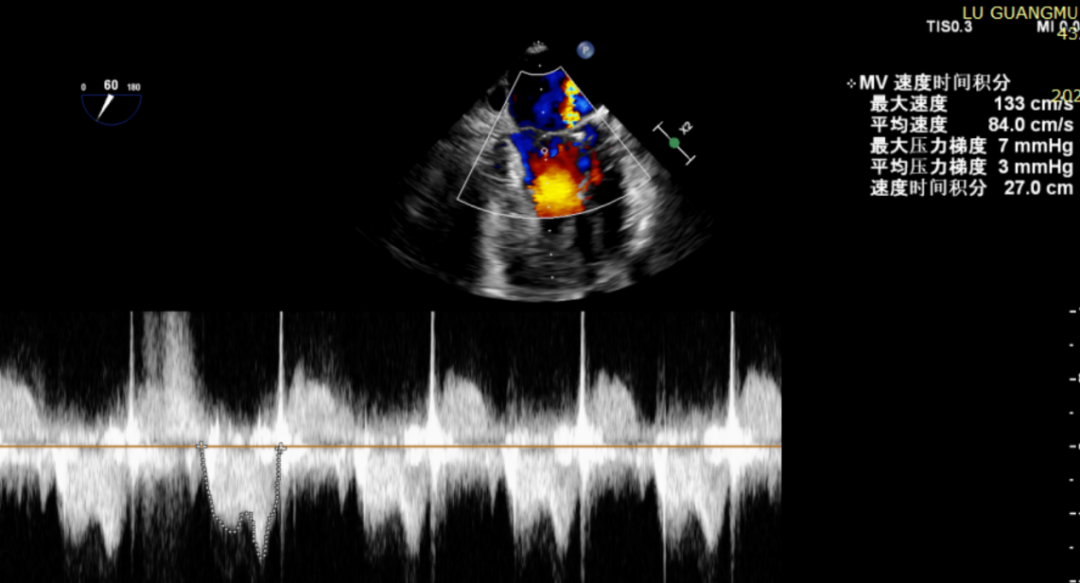

患者全麻后在超声和射线引导下穿刺股静脉-房间隔,器械顺利到达病变的二尖瓣区域,成功完成二尖瓣夹合后,患者二尖瓣反流即刻显著下降,左房压力即刻减低,预示着患者的临床症状将会得到明显改善。